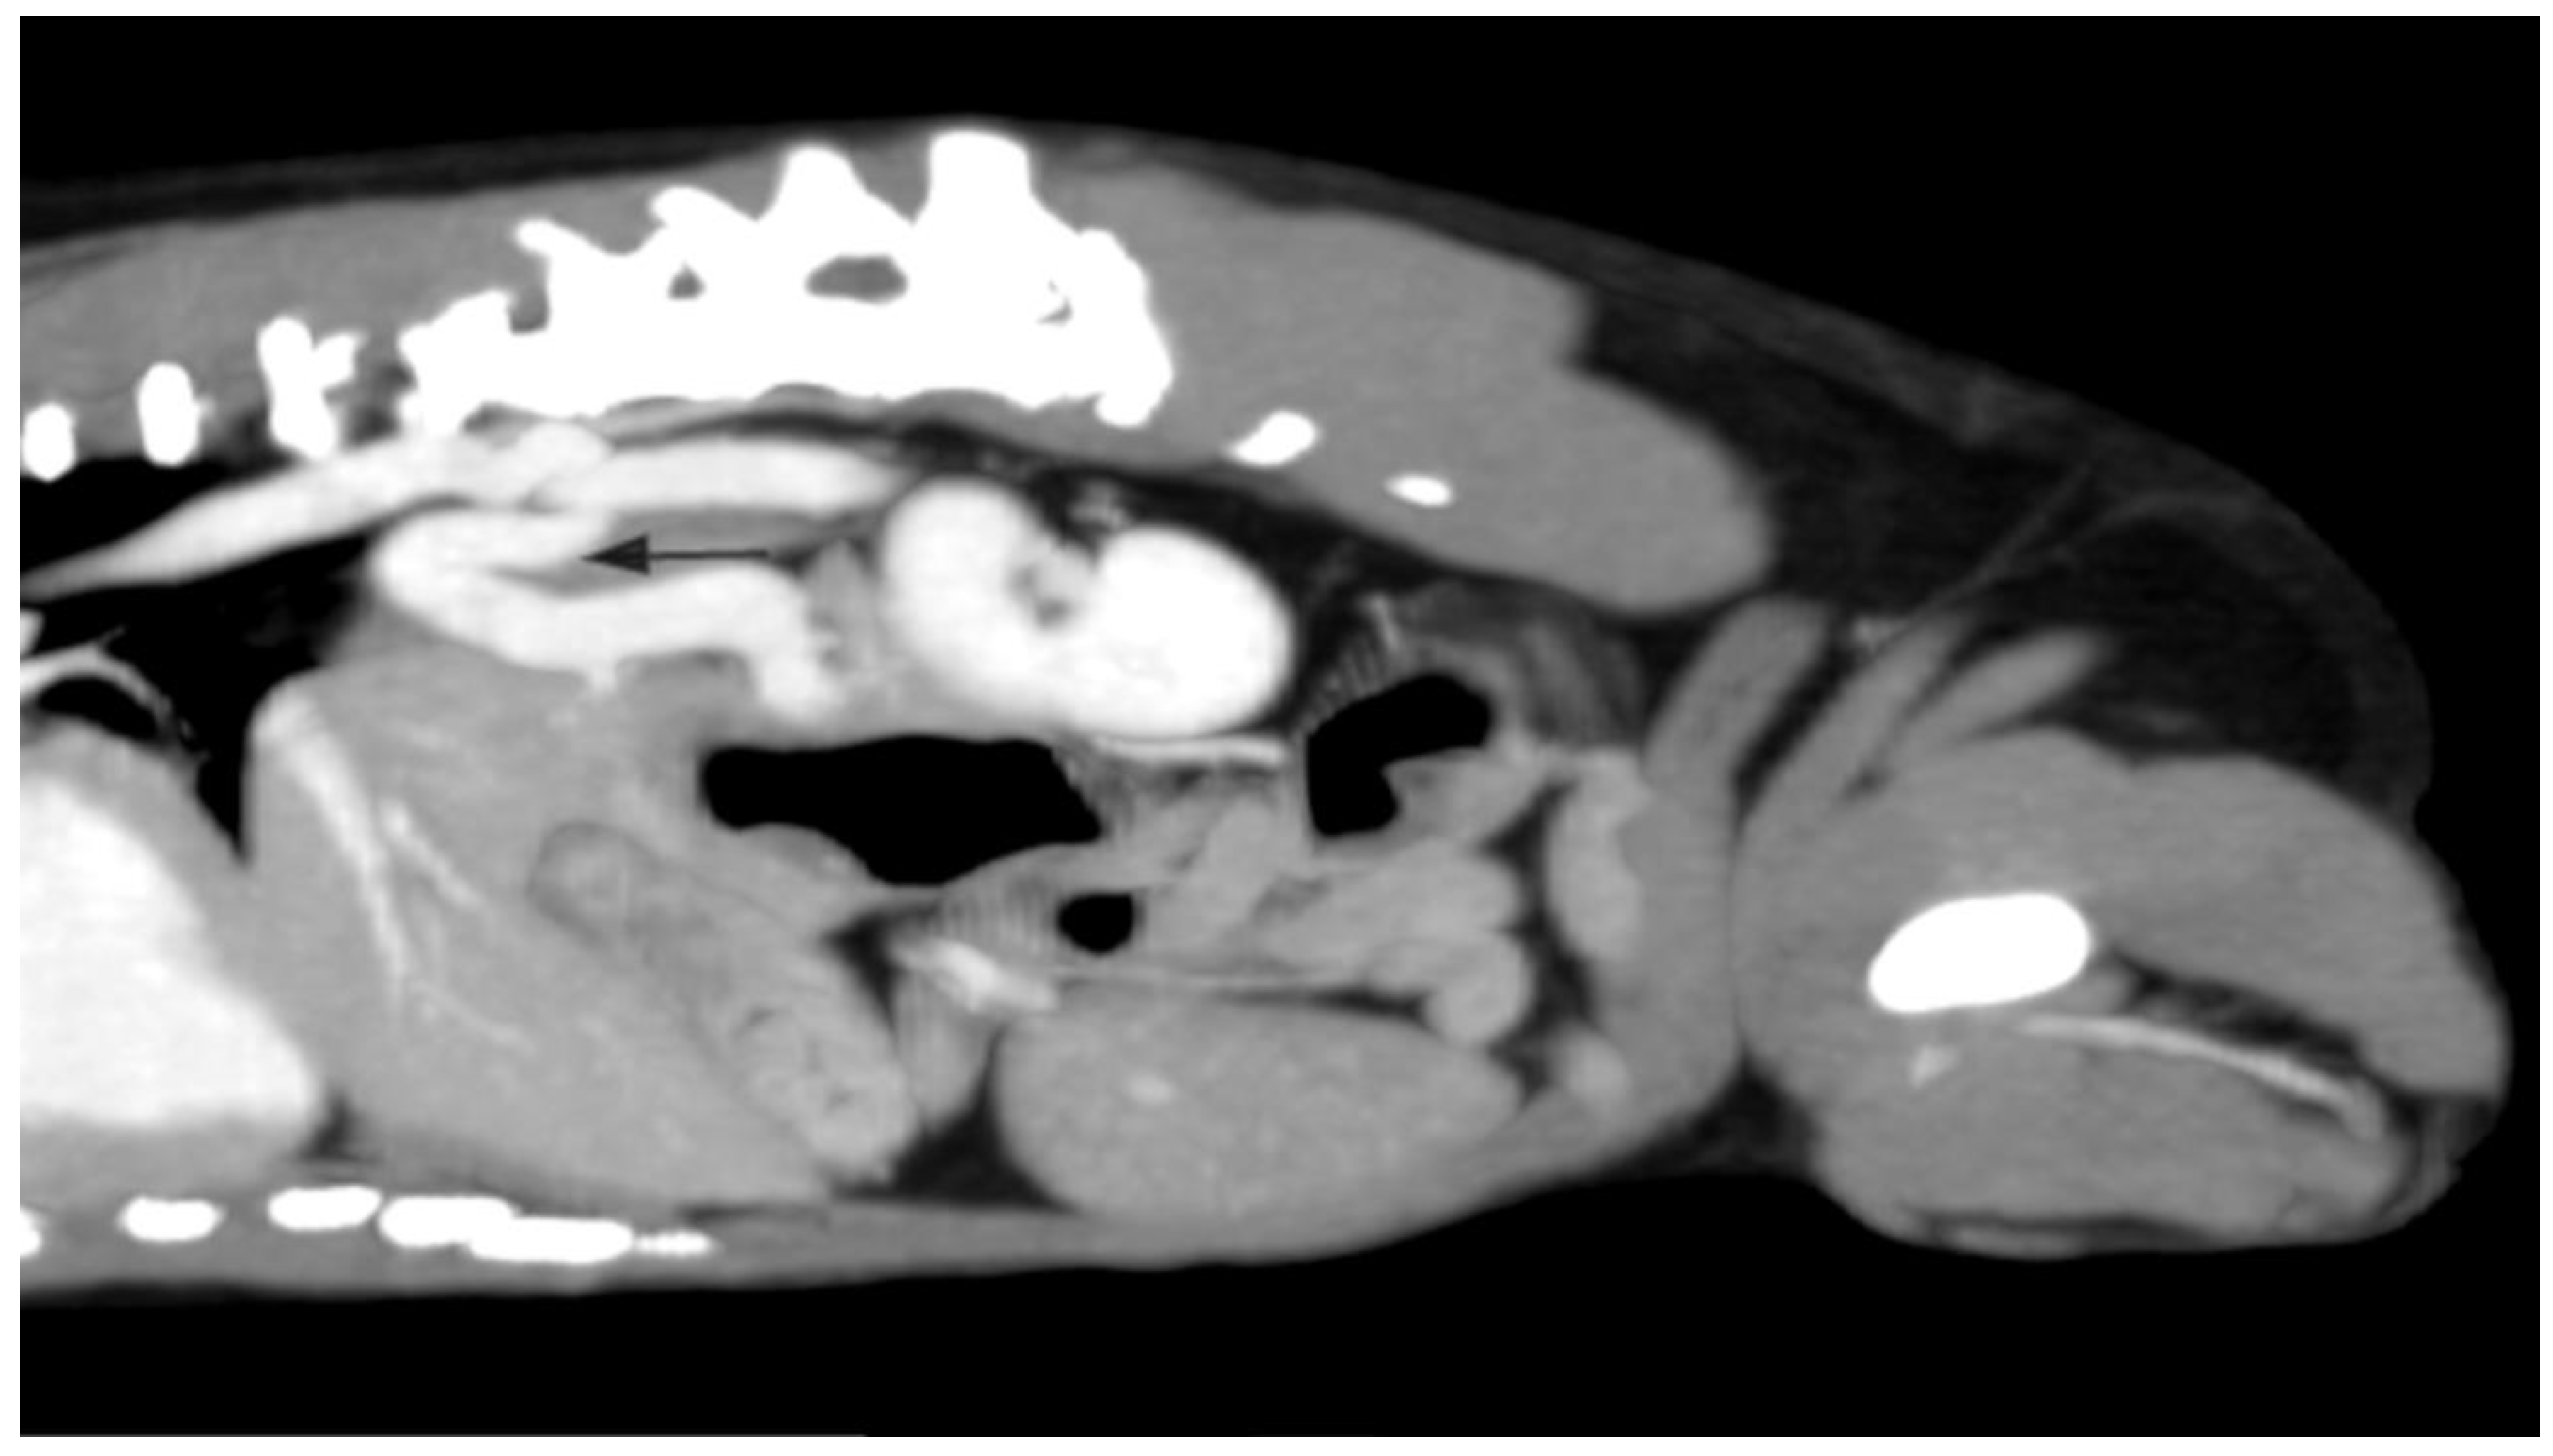

2.1. Case A (Human)

2.2. Case B (Human)